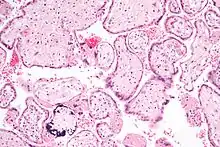

| CMV infection of a human lung pneumocyte | |

CMV infection can be demonstrated microscopically by the detection of intranuclear inclusion bodies. On H&E staining, the inclusion bodies stain dark pink and are called "owl's eye" inclusion bodies.[45]

Lytically replicating viruses disrupt the cytoskeleton, causing massive cell enlargement, which is the source of the virus' name.